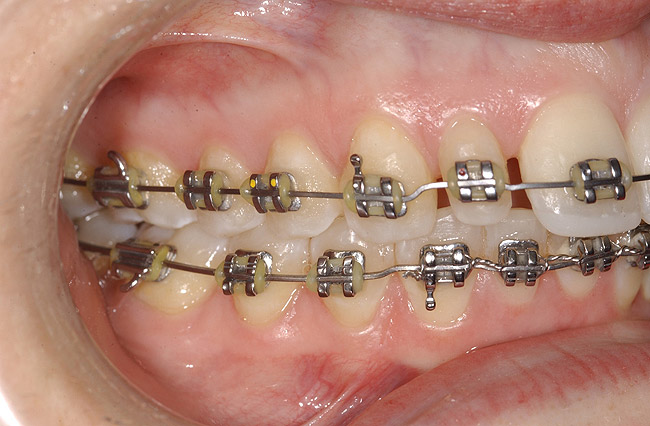

Figure 9: Orthodontic distraction osteogenesis to develop the implant site of tooth No. 23.

Figure 9

Figure 10  Radiograph of orthodontic distraction osteogenesis.

Figure 10

Figure 11  Radiograph showing developed implant site of tooth No. 23.

Figure 11

Figure 12  Right buccal view showing posterior occlusion established, canine guidance and proper space appropriation around peg lateral tooth No. 7, and intruded worn incisors.

Figure 12